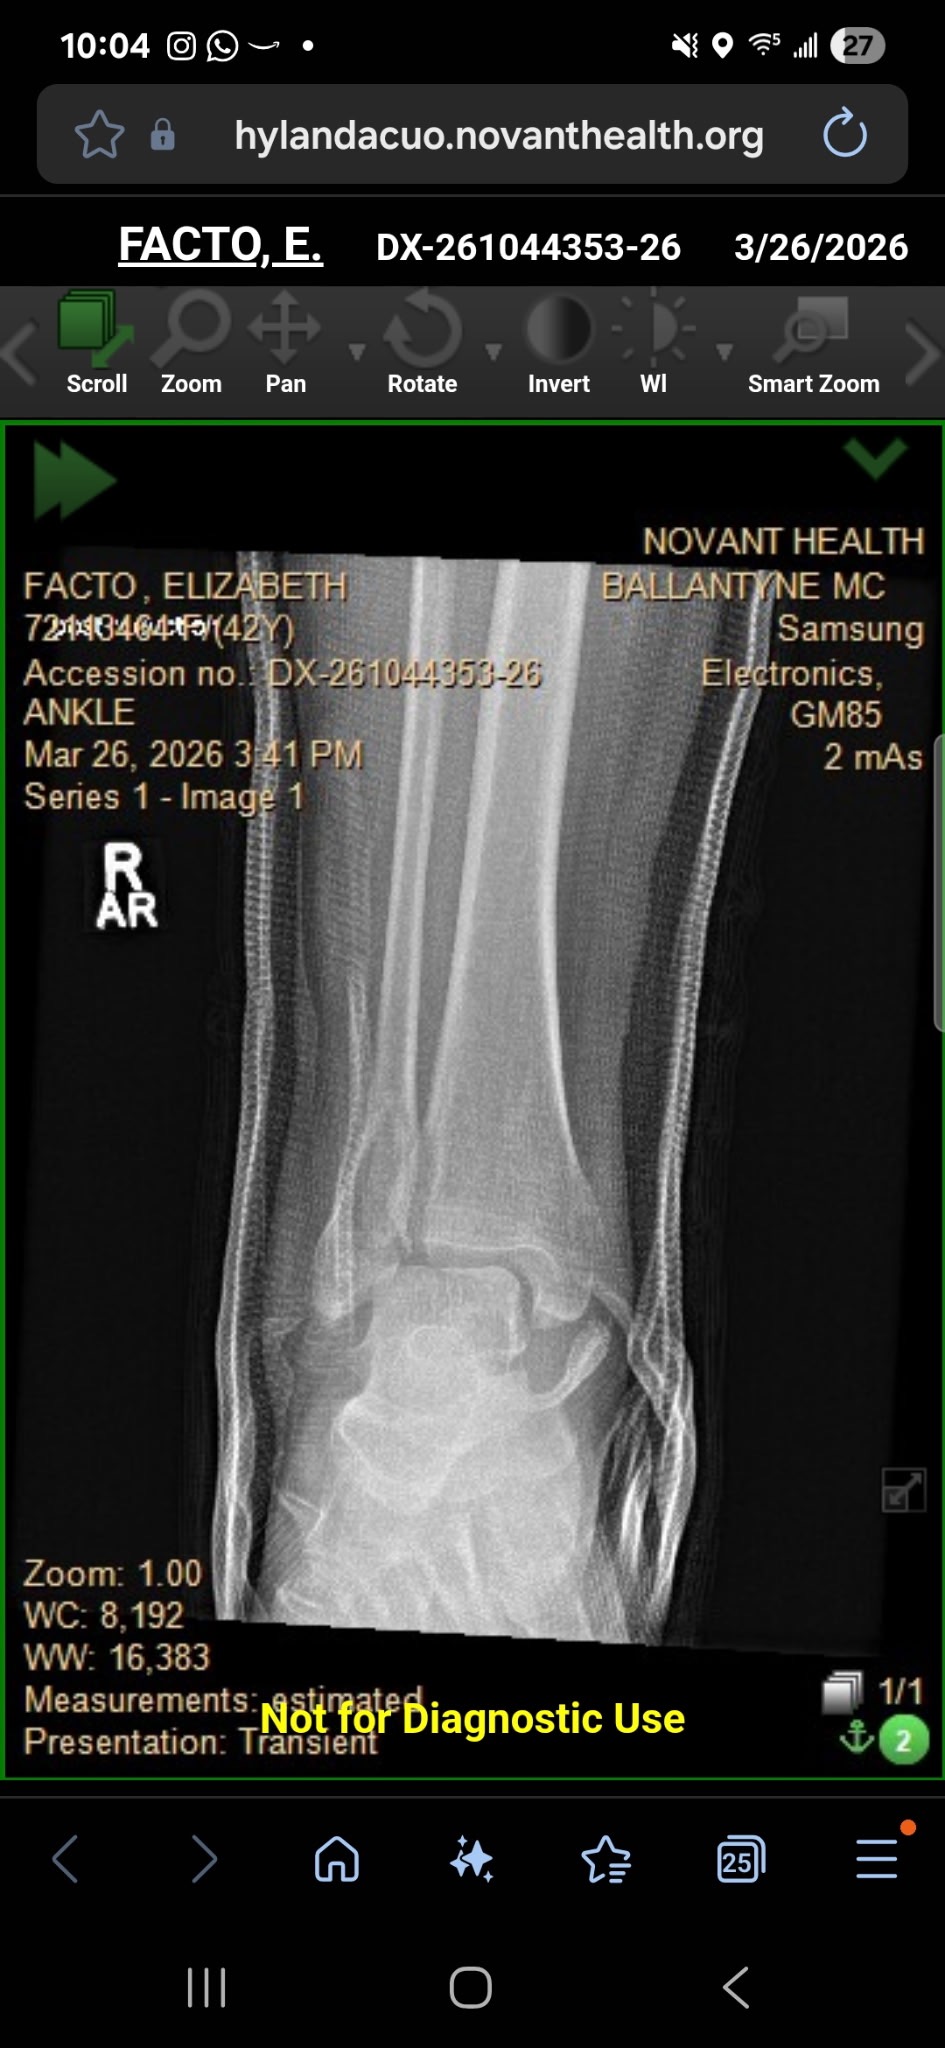

Our dear friend Elizabeth Facto has been through more than most could imagine in such a short time. Just months after courageously fighting and overcoming breast cancer, she has now suffered a serious accident—breaking her foot/ankle in three places.

Elizabeth will need surgery followed by months of rehabilitation, making it impossible for her to work during this time. As she focuses on healing, she is also facing overwhelming medical bills and the stress of lost income.